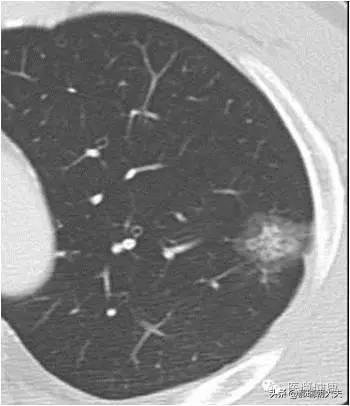

Les examens médicaux étant de plus en plus fréquents, les nodules pulmonaires sont de plus en plus souvent détectés. Les nodules pulmonaires sont un terme d'imagerie, et la définition d'imagerie d'un nodule pulmonaire est une petite lésion bien définie qui est complètement entourée par le parenchyme pulmonaire (Diamètre ≤30mm). La morphologie des nodules est classée comme solide ou sub-solide ; les nodules sub-solides sont eux-mêmes classés en nodules de verre dépoli et en nodules partiellement solides. Les lésions de plus de 30 mm de diamètre sont des masses plutôt que des nodules et ont une probabilité plus élevée d'être malignes.

La définition actuellement acceptée d'un nodule pulmonaire est une ombre pulmonaire focale, arrondie, hyperdense, solide ou subsolide, d'un diamètre ≤3 cm. Ces dernières années, avec l'augmentation de la population examinée par tomodensitométrie à faible dose, la proportion de nodules pulmonaires multiples détectés en plus des nodules pulmonaires isolés a considérablement augmenté. Les nodules pulmonaires multiples se présentent souvent sous la forme d'un nodule pulmonaire unique accompagné d'un ou plusieurs petits nodules. Les nodules pulmonaires multiples sont définis comme 2 lésions ou plus. Les patients présentant des nodules pulmonaires multiples peuvent avoir plusieurs sources de cancer du poumon précoce ou de lésions précancéreuses confirmées chirurgicalement et nécessitant une attention clinique particulière.

Nodules pulmonaires : Il s'agit de lésions qui apparaissent dans les tissus des poumons. Il s'agit de lésions arrondies ou irrégulières d'un diamètre inférieur ou égal à 30 mm, souvent entourées de tissu pulmonaire normal. Sur l'imagerie médicale, ils sont décrits comme des "ombres hyperdenses dans les poumons". Les nodules pulmonaires peuvent être uniques ou multiples, avec des limites claires ou floues.

En fonction de l'uniformité de la densité des nodules, on peut les classer en nodules substantiels, en nodules de verre dépoli purs et en nodules de verre dépoli mixtes.